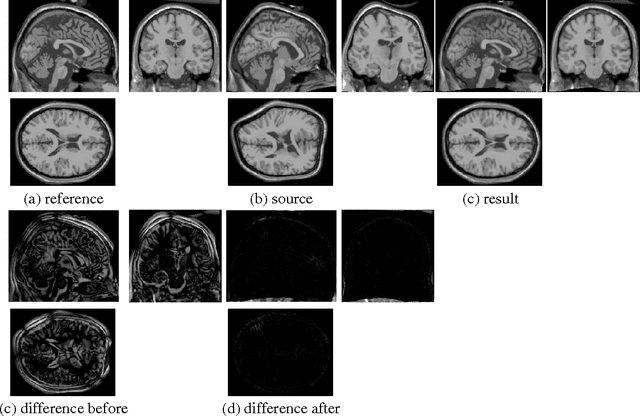

Abstract:We introduce an adaptive regularization approach. In contrast to conventional Tikhonov regularization, which specifies a fixed regularization operator, we estimate it simultaneously with parameters. From a Bayesian perspective we estimate the prior distribution on parameters assuming that it is close to some given model distribution. We constrain the prior distribution to be a Gauss-Markov random field (GMRF), which allows us to solve for the prior distribution analytically and provides a fast optimization algorithm. We apply our approach to non-rigid image registration to estimate the spatial transformation between two images. Our evaluation shows that the adaptive regularization approach significantly outperforms standard variational methods.